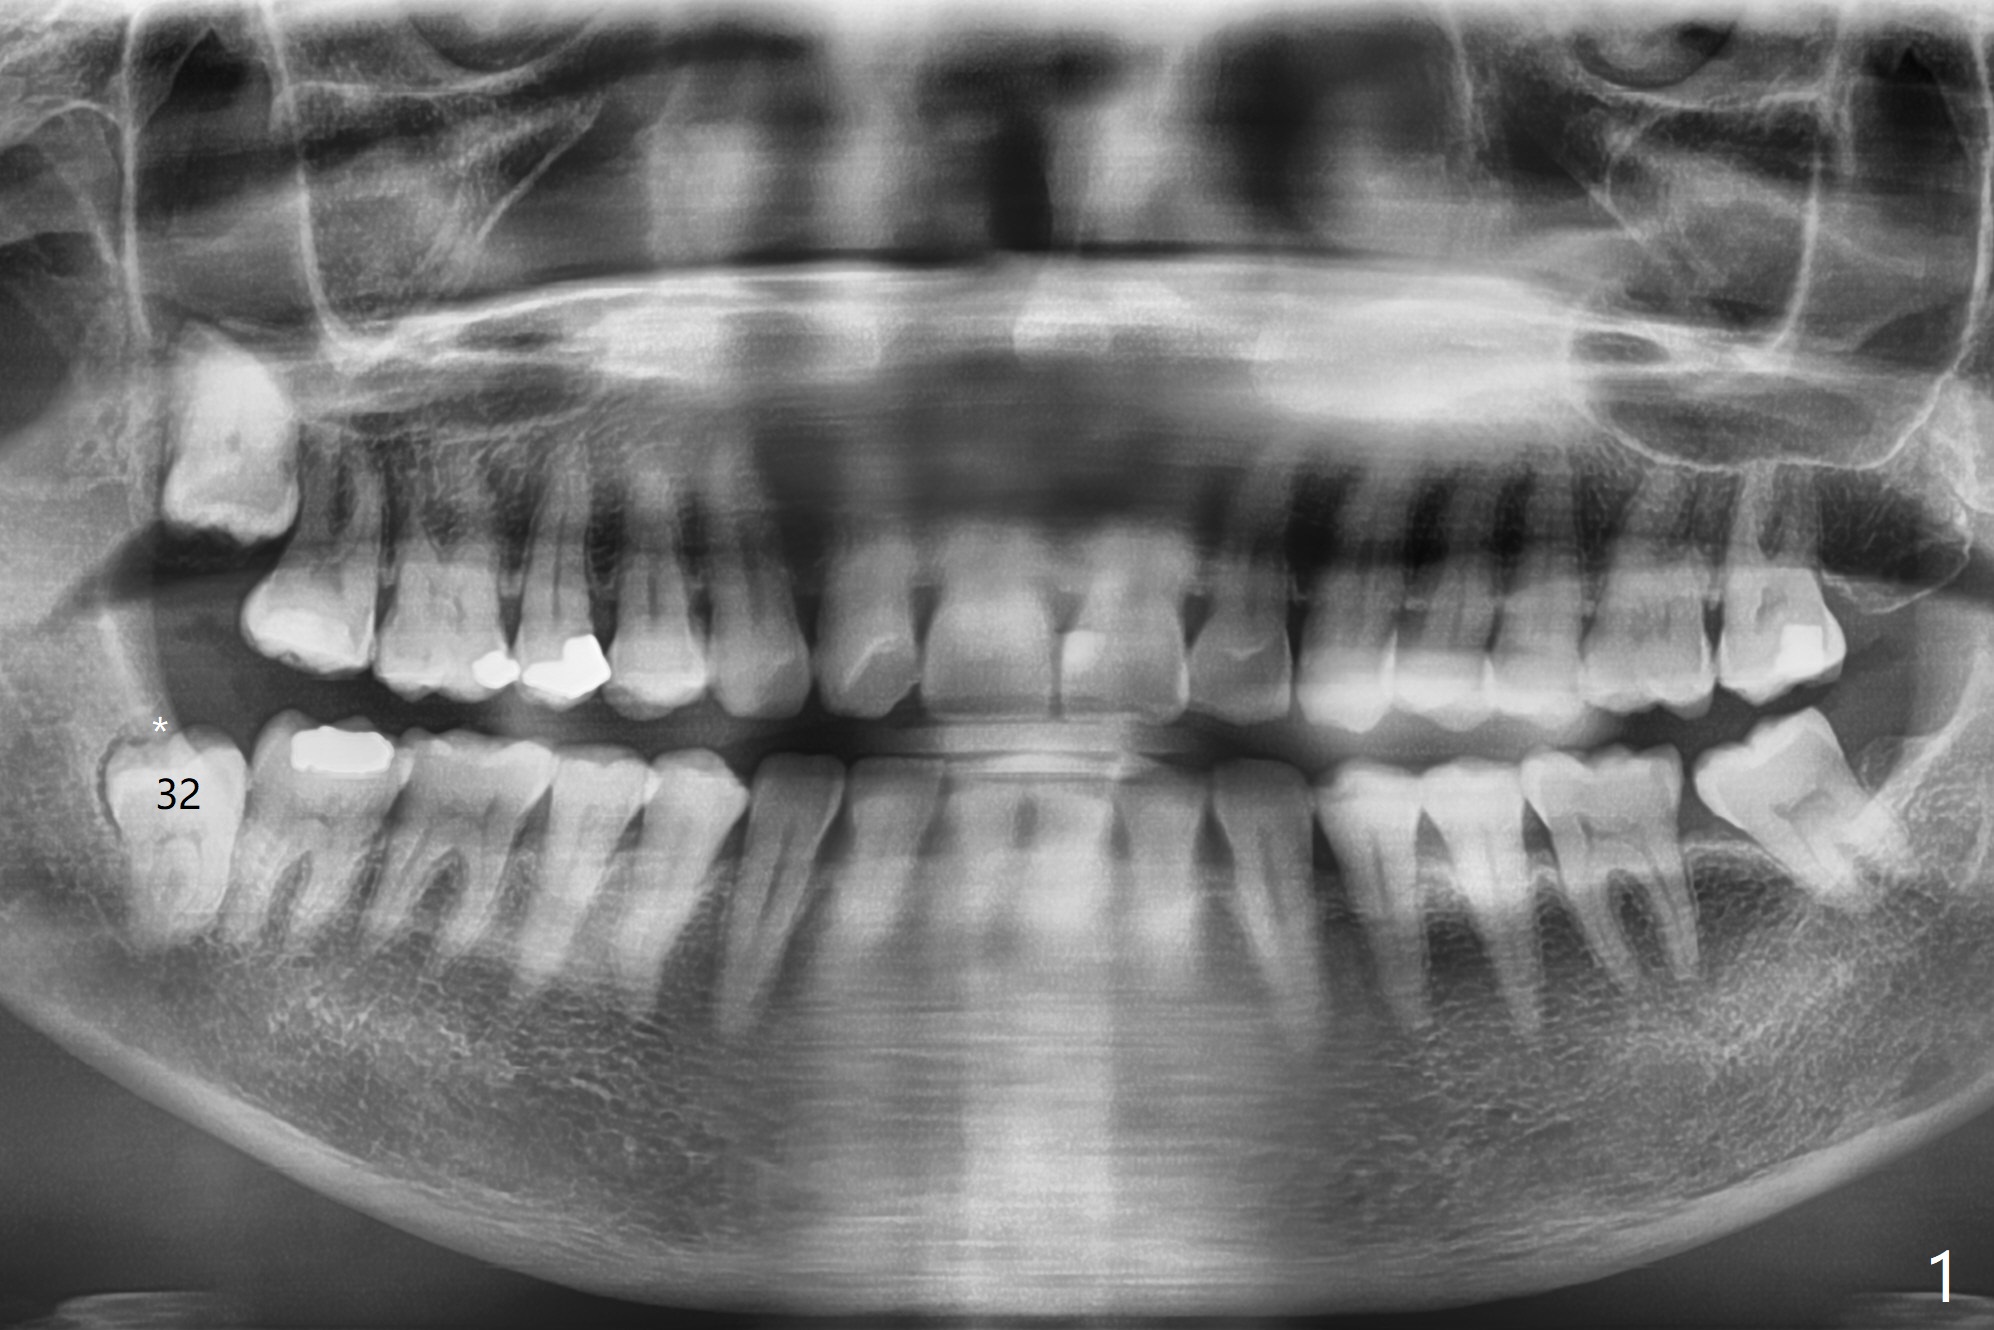

56岁女因右下智齿牙龈出血要求拔除,切开后发现智齿周围骨质吸收,有许多肉芽组织(图一:*),拔除容易,清创时远中牙龈出血,需要压迫止血,